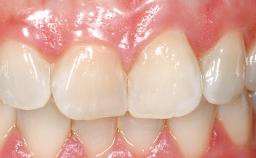

A 30-year-old female patient had lost tooth 21 and was referred to our clinic for consultation and treatment. Due to advanced apical infection, tooth 21 had been extracted two months earlier at another clinic and an acrylic-resin tooth had been bonded to the adjacent teeth. The patient desired implant treatment to avoid any damage to the adjacent natural teeth. While the patient had no history of any systemic disorder, she was a heavy smoker and exhibited medium to advanced periodontitis in the entire jaw. After the initial treatment to achieve a pocket probing depth of less than 4 mm and no bleeding on probing, a decrease in the height of the papillae mesial and distal to the extraction site and overall gingival recession were observed.

| Soft Tissue Grafting | Simultaneous |

| Abutment Type | CAD/CAM |

| Prosthesis Type | FDP |